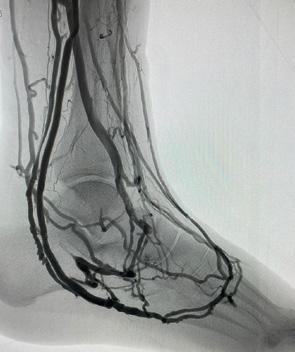

Ons lichaam beschikt over bloedvaten die zuurstof en voedingsstoffen naar onze organen en ledematen brengen. Bij kritieke ledemaatischemie zijn de bloedvaten in het been — vooral de slagaders — zo zwaar aangetast door aderverkalking dat er nauwelijks nog zuurstofrijk bloed in de voet komt (Figuur 1). Dat veroorzaakt pijn in rust of ‘s nachts en wondjes die niet genezen. Zonder behandeling ontstaat weefselversterf (gangreen), met een verhoogd risico op infectie, amputatie en overlijden.

Bij de meeste patiënten kunnen we de doorstroming verbeteren. Afhankelijk van de ernst en de locatie van deze verstoppingen kiezen we voor een ballondilatatie (Percutane Transluminale Angioplastiek of PTA) of een overbruggingsoperatie (bypass) (Figuur 2a en b). Bij een kleine groep patiënten – vaak met diabetes en/of chronisch nierlijden – zijn de bloedvaten in het onderbeen en de allerkleinste vaatjes in de voet zo ernstig verstopt dat klassieke technieken geen haalbare optie zijn.

GEBLOKKEERDE SLAGADER

Bij diep veneuze arterialisatie (DVA) draaien we als het ware het systeem om. In plaats van het bloed via slagaders (arteries) naar de voet te brengen, leiden we het zuurstofrijke bloed rechtstreeks in de diepe aders (venen) van het onderbeen en de voet. Normaal brengen deze aders het bloed terug naar het hart, maar na deze ingreep kan zuurstofrijk bloed via dit netwerk naar de voet stromen en zo de weefsels opnieuw voeden. Het doel? Wondgenezing stimuleren en amputaties vermijden, zelfs als er geen arteriële doorgangen meer beschikbaar zijn.

Diep veneuze arterialisatie is geen standaardbehandeling, maar een laatste redmiddel voor patiënten waarbij alle klassieke opties zijn uitgeput. Door middel van deze ingreep proberen we een amputatie van het onder- of bovenbeen te vermijden. Voor de procedure onderga je een grondig preoperatief onderzoek om te bepalen of veneuze arterialisatie geschikt is voor jouw specifieke situatie.

De procedure vindt plaats in onze hybride operatiezaal onder algemene verdoving. Via kleine prikken in de lies en de voet worden een slagader en een diepe ader met elkaar verbonden — dit noemen we een arterioveneuze (AV) fistel. Vervolgens plaatsen we een stent die het bloed richting voet leidt (Figuur 4, voor en na).

Na deze eerste ingreep heeft het lichaam tijd nodig om zich aan te passen. Gedurende 6 à 8 weken volgt een rijpingsproces waarbij het aderlijk netwerk zich verder ontwikkelt en connecties maakt met het slagaderlijk netwerk (Figuur 5, voor en na). Tijdens deze periode doen we regelmatige controles middels echografie om te beoordelen of de nieuwe doorstroming goed functioneert. Meestal is nog een tweede ingreep nodig om kleine zijtakjes af te sluiten, zodat het bloed verder richting de voet kan worden gestuurd.

Nauwkeurige opvolging is dus cruciaal. We combineren medische beeldvorming met gespecialiseerde wondzorg. Vaak is een beperkte ingreep nodig om afgestorven

weefsel (bv. een teen of een deel van de voet) te verwijderen. Deze kleine amputatie wordt meestal pas uitgevoerd wanneer de bloedvoorziening voldoende hersteld is — ten vroegste 6 à 8 weken na de DVA.

Genezing van chronische voetwonden duurt vaak maanden, maar het belangrijkste is dat we bij ongeveer 60 tot 70% van de patiënten een amputatie van het onder- of bovenbeen kunnen voorkomen. DVA is geen ‘mirakeloplossing’, maar biedt wél hoop voor patiënten bij wie klassieke ballondilatatie/stent of bypass tot voor kort geen uitweg meer bood.